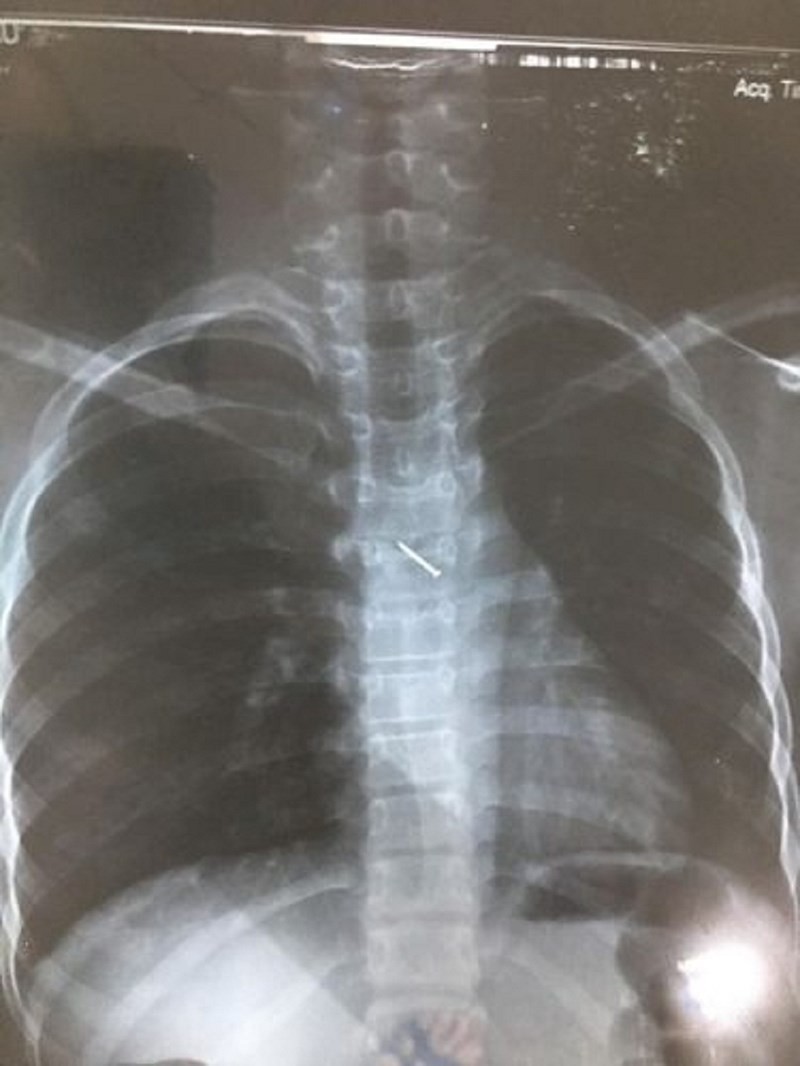

Sau sự cố, bé ho sặc sụa, khạc ra máu, nôn nhiều nên được người nhà đưa đến bệnh viện đa khoa Mộc Châu (Sơn La) khám. Tại đây, qua chụp X-quang các bác sĩ xác định lồng ngực bệnh nhân có dị vật hình đinh ghim. Bệnh nhân được chuyển tới BV Nhi Trung ương để theo dõi và tiếp tục điều trị.

Tại BV Nhi Trung ương, hình ảnh chụp X-quang cho thấy có dị vật là một chiếc đinh ghim dài khoảng 1,5cm nằm ở vị trí thành ngực của bệnh nhân. Các bác sĩ đã hội chẩn và quyết định phẫu thuật nội soi lấy dị vật.